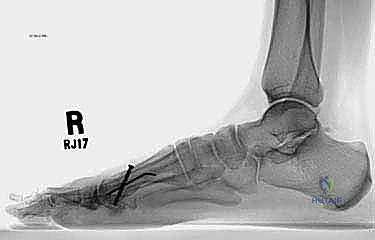

* الأشعة السينية العادية (X-rays) أثناء الوقوف: هذا هو الفحص الأهم. يتم أخذ صور للقدمين أثناء تحمل الوزن لقياس زوايا العظام بدقة، وتحديد مقدار النقص في طول مشط القدم الأول مقارنة بالثاني (يجب أن يكونا متقاربين في الطول ضمن نسب محددة).

2. التصوير الشعاعي المتقدم

التصوير هو ما يظهر الحجم الحقيقي للمشكلة الهيكلية.